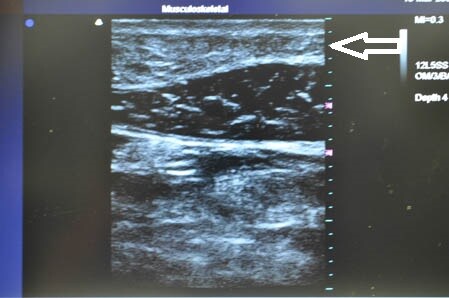

上記の画像の部分をつまんでみましょう。

同様に下腹部も見ておきましょう。

↓ ↓ ↓